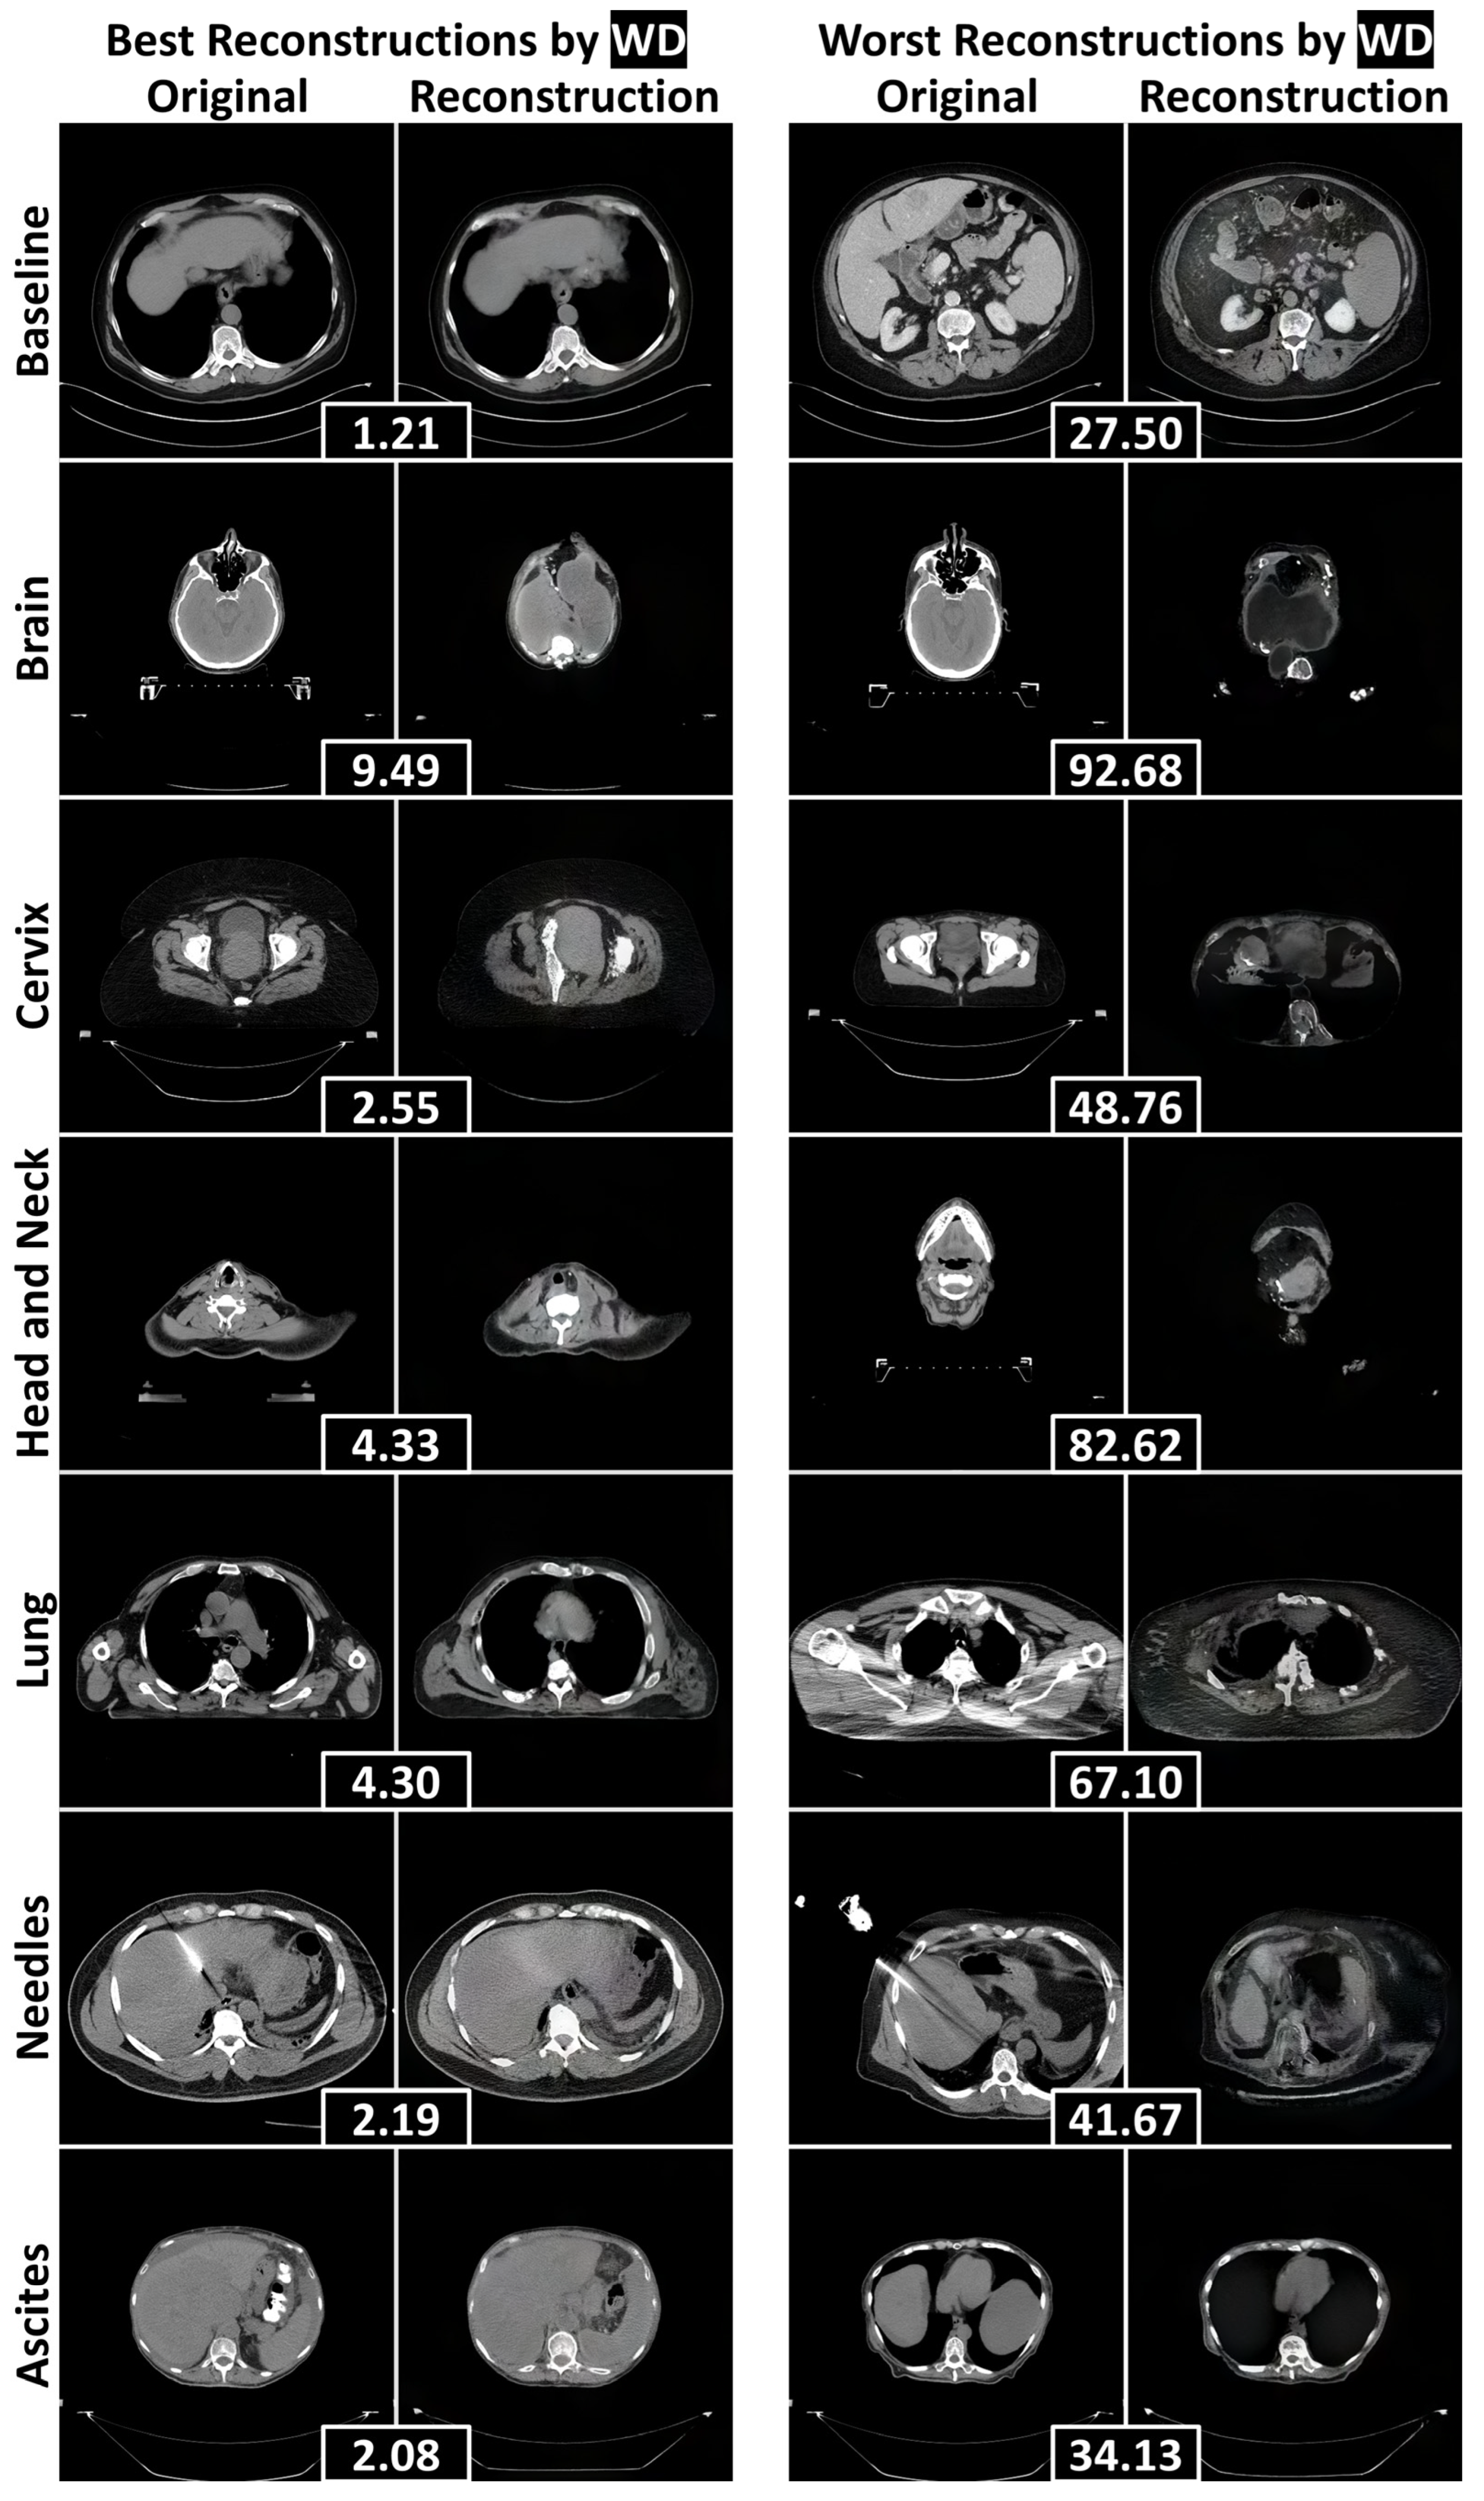

3.2. Reconstruction Performance and Interpretation